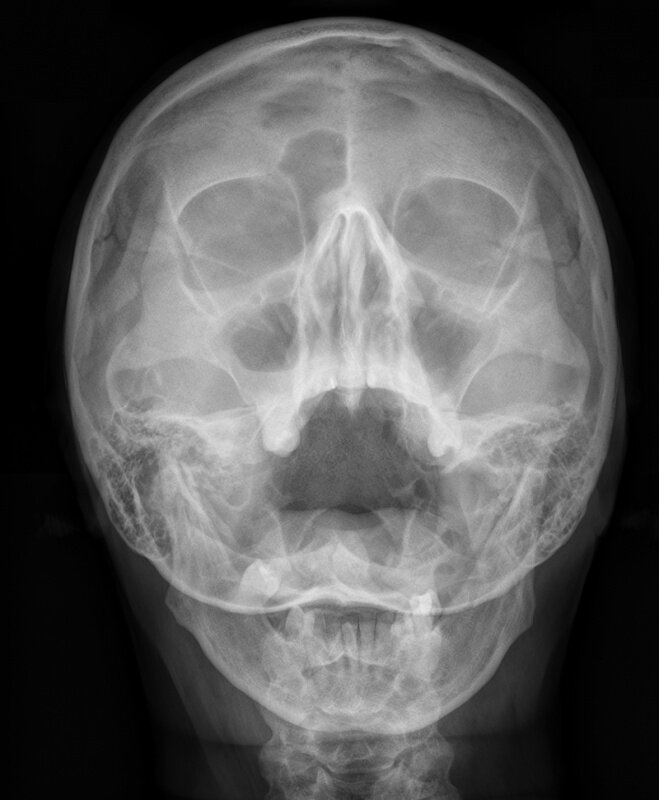

Утолщение слизистой оболочки гайморовых пазух с обеих сторон, справа - горизонтальная тень, скорее всего - патологическая жидкость, о содержимом будет известно после пункции. Фото для примера из Интернета.